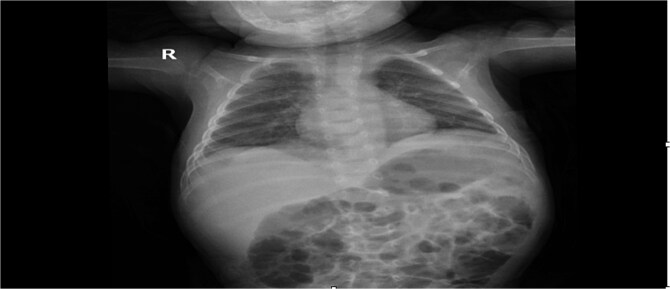

先天性膈疝(CDH)是一种罕见但可能危及生命的异常,由胎儿发育期间膈肌不完全闭合引起,通常在新生儿出现,但很少在婴儿期后期表现为紧张性胃胸,这是胸内胃疝和胃胀的一种严重的症状,可引起严重的呼吸窘迫和纵隔移位;我们描述了一个2个月大的男婴,由于左侧Bochdalek疝,胃扩张占据胸腔,出现突发性呼吸困难和纵隔移位,需要紧急剖腹手术,胃减压和使用不可吸收缝线修复缺陷,导致全肺重新扩张和恢复;本病例强调了晚期CDH合并紧张性胃胸的诊断和治疗挑战,将其与其他呼吸窘迫原因区分开来的重要性,并强调及时识别,及时减压和手术修复对于获得良好结果至关重要,敦促临床医生在影像学显示窘迫婴儿充满空气的半胸时保持高度怀疑。

Congenital diaphragmatic hernia (CDH), a rare but potentially life-threatening anomaly resulting from incomplete diaphragm closure during fetal development, typically presents neonatally but can rarely manifest later in infancy as tension gastrothorax-a critical condition of intrathoracic gastric herniation and distension causing severe respiratory distress and mediastinal shift; we describe a 2-month-old male infant who developed sudden dyspnea and mediastinal shift due to a left-sided Bochdalek hernia with a distended stomach occupying the thoracic cavity, requiring emergent laparotomy with gastric decompression and defect repair using non-absorbable sutures, leading to full lung re-expansion and recovery; this case highlights the diagnostic and therapeutic challenges of late-presenting CDH complicated by tension gastrothorax, the importance of distinguishing it from other causes of respiratory distress, and emphasizes that prompt recognition, timely decompression, and surgical repair are vital for favorable outcomes, urging clinicians to maintain high suspicion when imaging reveals an air-filled hemithorax in distressed infants.